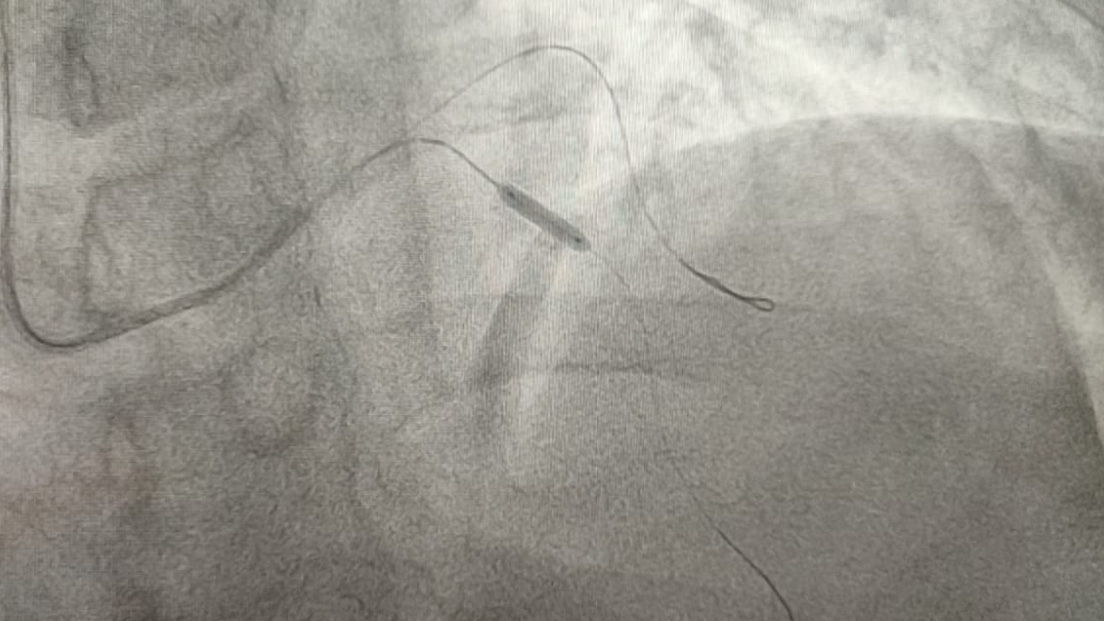

A través de un procedimiento de angioplastia coronaria y la colocación de estents en la nueva Unidad de Hemodinamia, se logró abrir las arterias que tenía obstruidas y restablecer su flujo de sangre.

Esto permitió que, posteriormente, el varón fuera trasladado a la nueva Unidad de Hemodinamia, donde se le brindó medicamento y se le realizó el procedimiento de alta especialidad para atender su afección cardiaca.

Con la activación del “Código Infarto”, el equipo multidisciplinario de la nueva Unidad de Hemodinamia se puso en marcha, e inició medicamento para deshacer el coagulo del paciente y darle recepción para la apertura de la arteria que se encontraba obstruida al 90 por ciento, lo cual impedía el paso de sangre al corazón.

Al culminar el procedimiento, se destapó la arteria, se colocó un medicamento especial para evitar una nueva oclusión y, de esta manera, el paciente recibió una nueva oportunidad de vida.